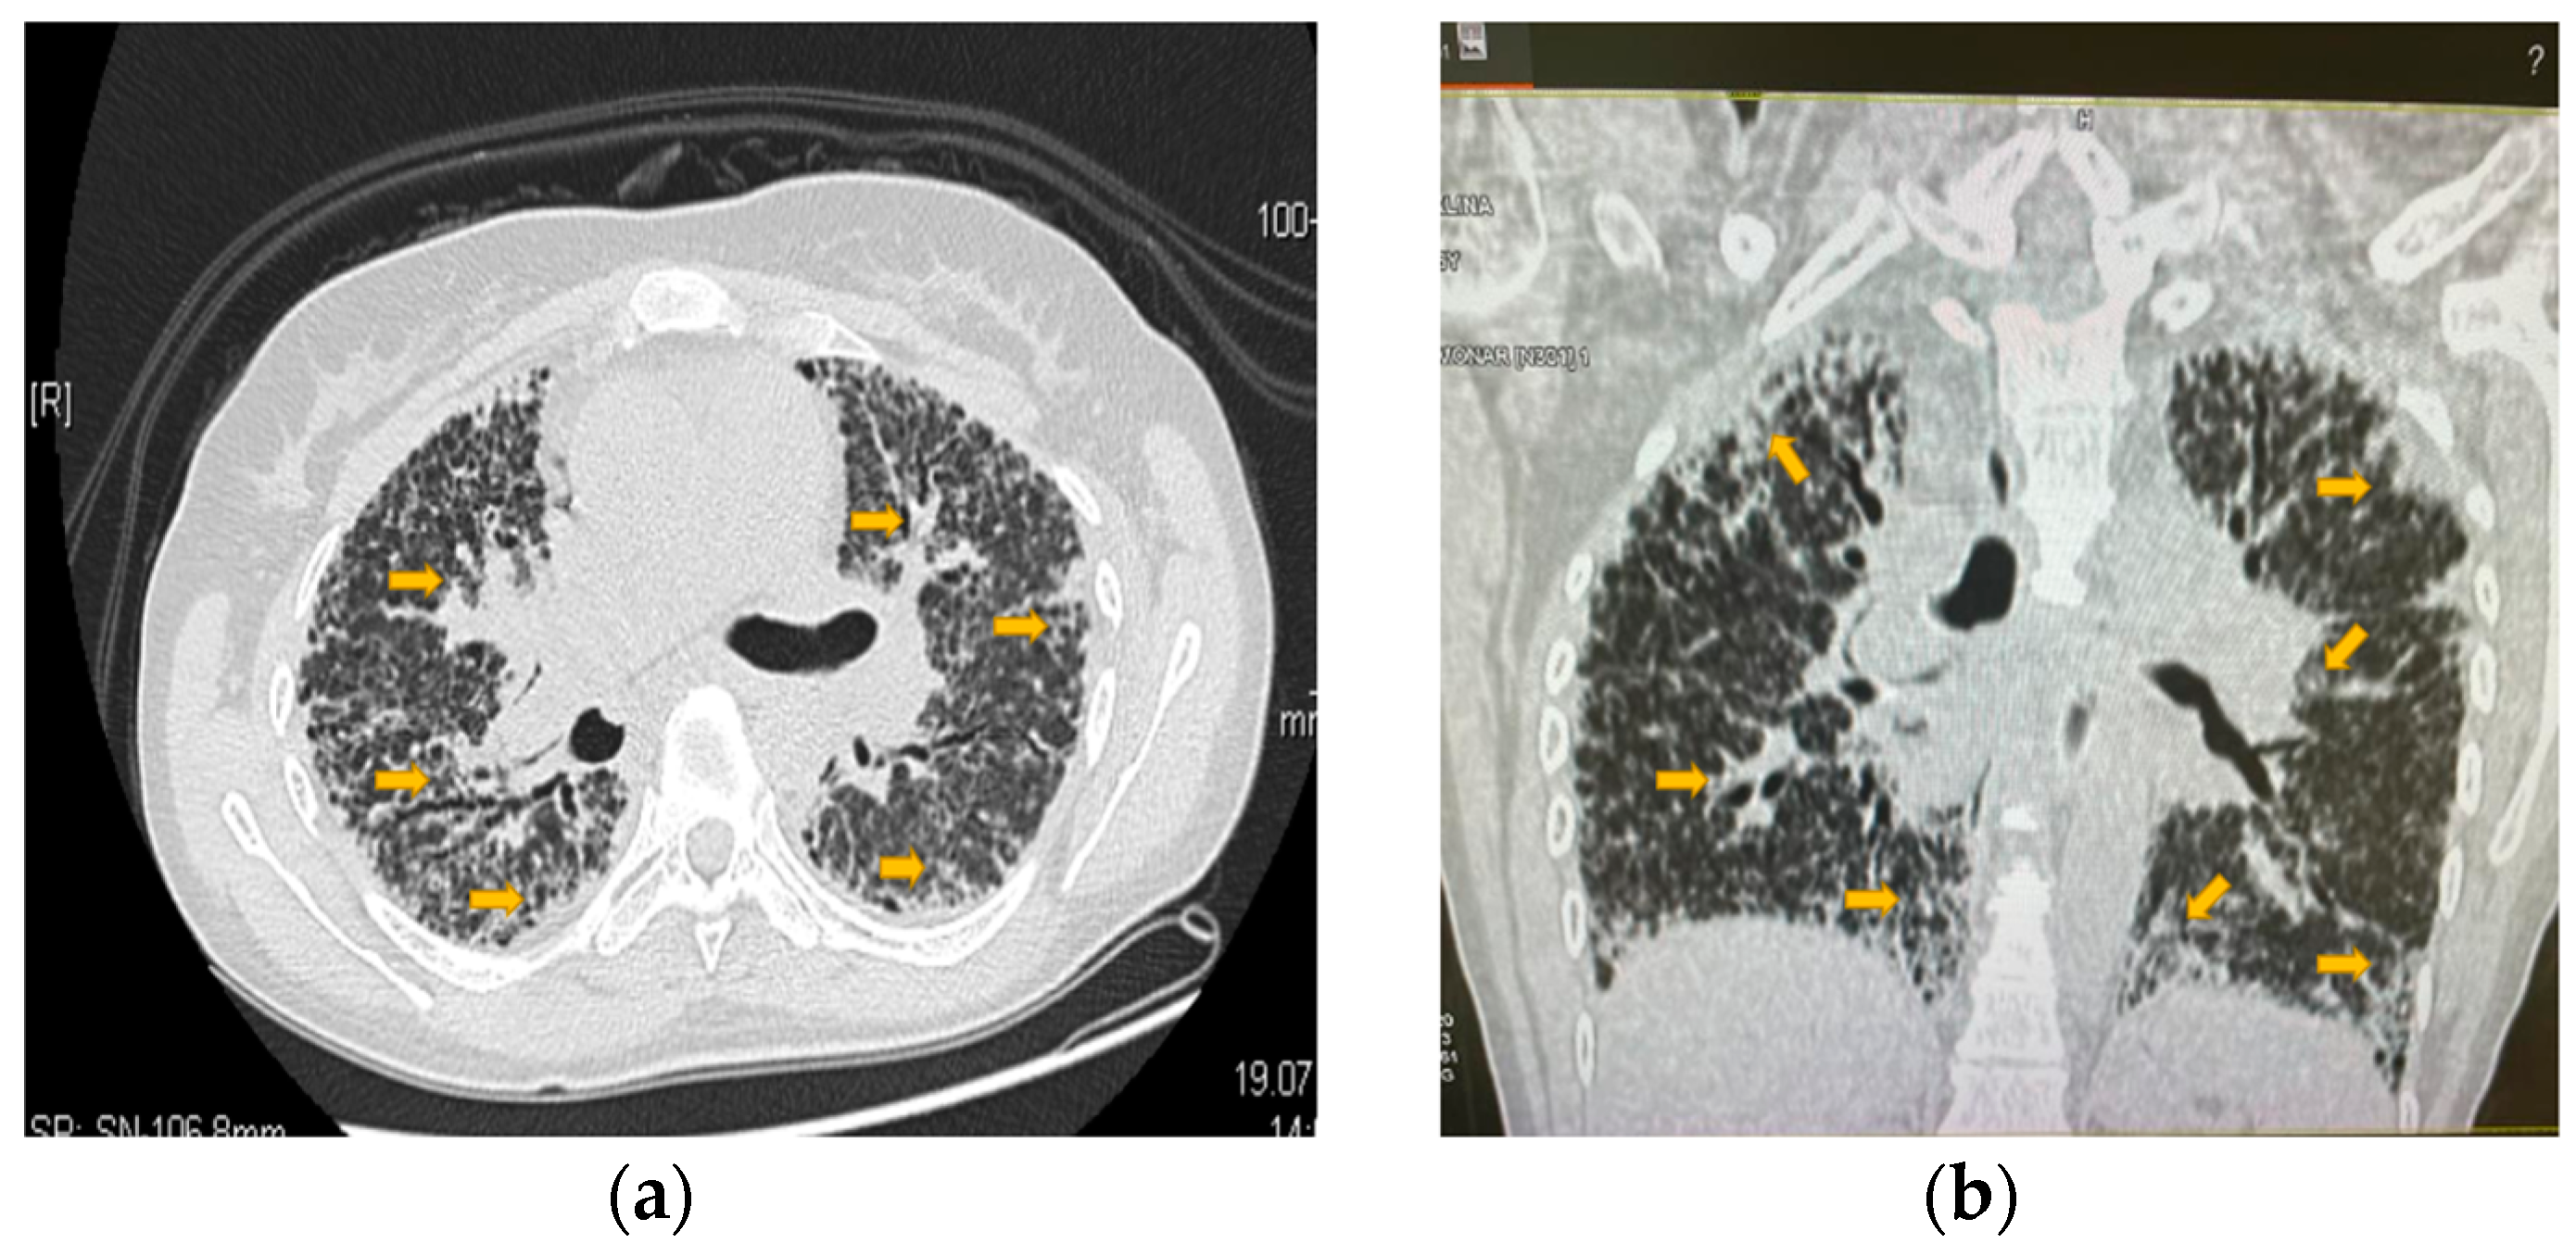

- Gupta, N.; Finlay, G.A.; Kotloff, R.M.; Strange, C.; Wilson, K.C.; Young, L.R.; Taveira-DaSilva, A.M.; Johnson, S.R.; Cottin, V.; Sahn, S.A.; et al. Lymphangioleiomyomatosis Diagnosis and Management: High-Resolution Chest Computed Tomography, Transbronchial Lung Biopsy, and Pleural Disease Management. An Official American Thoracic Society/Japanese Respiratory Society Clinical Practice Guideline. Am. J. Respir. Crit. Care Med. 2017, 196, 1337–1348. [Google Scholar] [CrossRef] [PubMed]